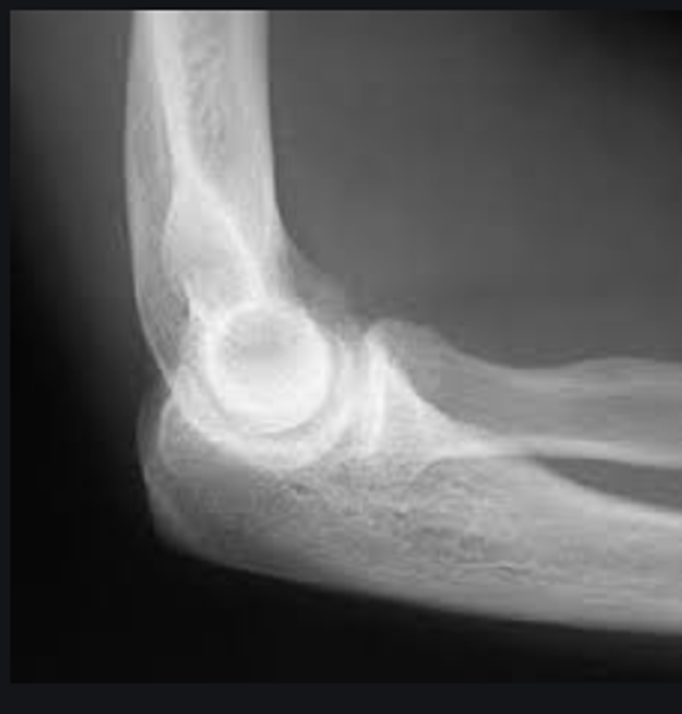

-All anatomy present

-Collimation is tight, want to open up some more

-Totally body positioning was not utilized because you cannot see the 3 concentric arches (trochlear notch, trochlear sulcus, ridges of the capitulum and trochlea)

-Not fully bent 90 degrees but close

-Coronoid process and radial head should be half superimposed (this image is a little more than half)

-Olecranon is in profile

-No marker

-REPEAT cause not in a true lateral position

Critique this lateral elbow image